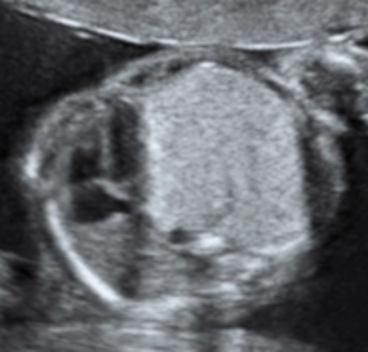

La CPAM viene agevolmente diagnosticata mediante l’esame ecografico in cui appare come un’area iperecogena disomogenea con all’interno possibili aree cistiche anecogene di diverse dimensioni, contenenti liquido. Tra le diverse classificazioni esistenti, quella attualmente più utile in ambito ecografico soprattutto per il suo significato prognostico, distingue le forme di CPAM in macrocistiche e microcistiche.

Immagini ecografiche di CPAM di tipo macrocistico (A), microcistico (B) e misto (C)